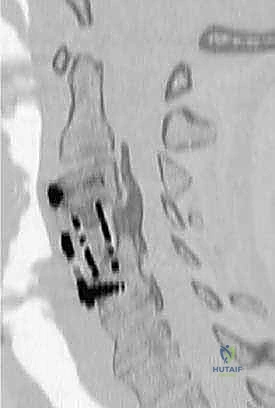

التصوير بالرنين المغناطيسي (MRI):

هو المعيار الذهبي لتشخيص اعتلال النخاع. يوضح الرنين المغناطيسي بوضوح شديد الحبل الشوكي، جذور الأعصاب، الأقراص الغضروفية، والأربطة. من خلال الرنين، يحدد الدكتور هطيف مستويات الانضغاط، وما إذا كان هناك تغير في إشارة الحبل الشوكي (Myelomalacia) مما يدل على تلف فعلي في أنسجة النخاع. -

التصوير المقطعي المحوسب (CT Scan):

يُستخدم بشكل خاص لتقييم التراكيب العظمية. وهو حيوي جداً في تشخيص حالات "تعظم الرباط الطولي الخلفي" (OPLL) وتحديد سماكة العظام قبل التخطيط لعملية رأب الصفيحة. -